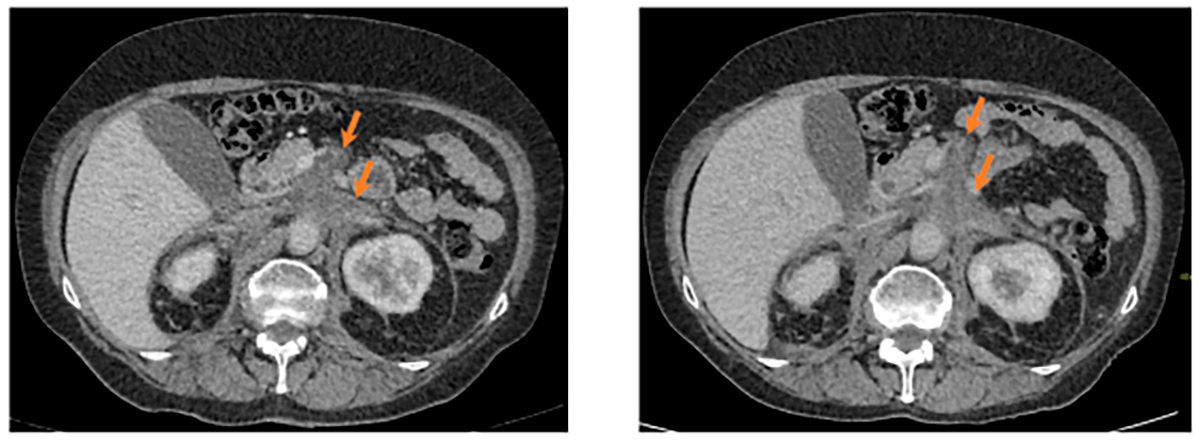

Рис. 6. Инфильтрация забрюшинной клетчатки, положительная динамика. Слева 2025 год, справа 2023 год. Аксиальная проекция.